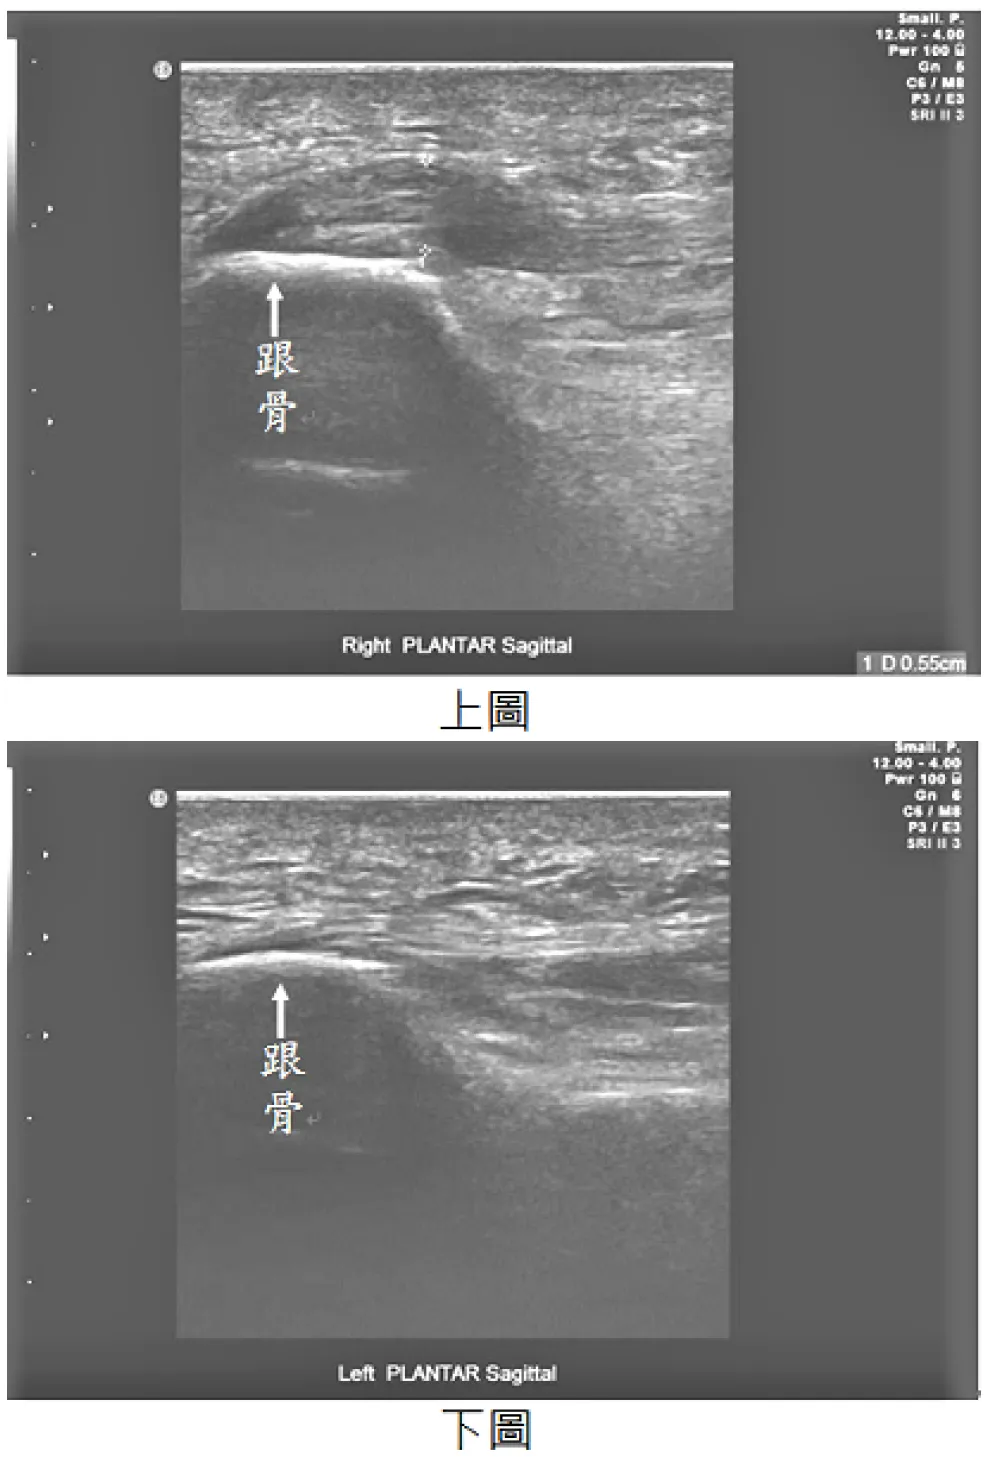

【112-2 醫學(六) 第74題】63歲女性病人,主訴右足底疼痛,於起床著地時特別明顯。超音波檢查如圖,上圖為右側足底筋膜連結至跟骨處,下圖為左側足底筋膜連結至跟骨處,最可能診斷為何?

這題的解題核心是將病人的典型症狀與超音波影像中足底筋膜的異常變化連結起來,尤其要注意右側足底筋膜明顯增厚。